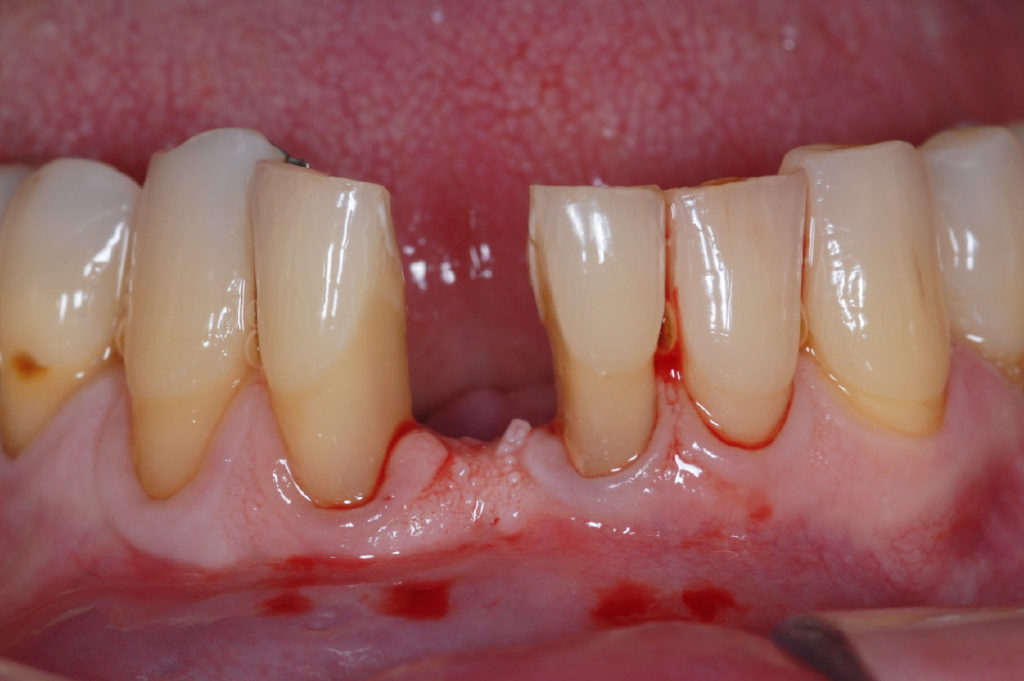

Sitio preoperatorio